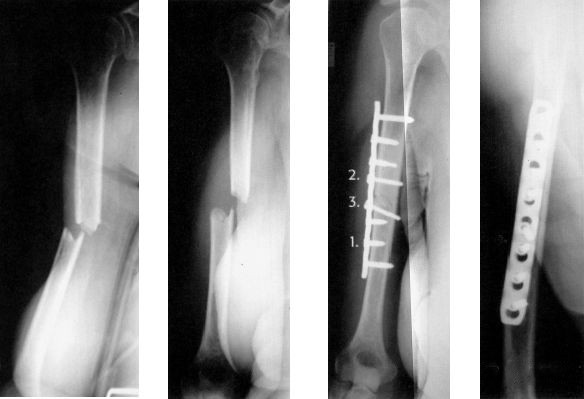

Когда блок перелома повреждает подключичную артерию, вену и плечевое сплетение, считается, что это серьезное осложнение и его следует оперировать немедленно.

При эластическом возврате происходит после мануального вправления сухожилия длинной двуглавой мышцы, когда появляются симптомы поражения подмышечного нерва.

Как только при медицинском осмотре будут обнаружены симптомы повреждения лучевого нерва, операция будет выполнена немедленно.